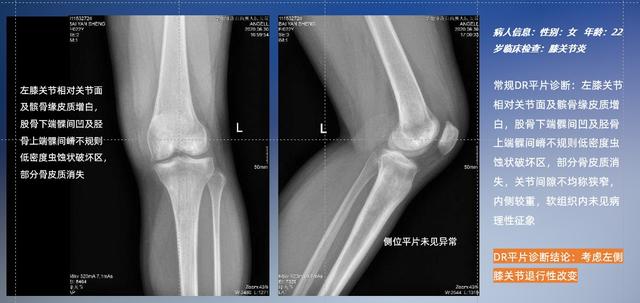

以膝关节疾病检查为例,膝关节在解剖学意义上是一种较为复杂的最大关节,由胫骨上端、股骨下端及髌骨组成。在股骨与胫骨的关节面之间存在两块半月板,分别处于内侧、外侧。膝关节的运动主要为伸、屈,在半屈位时可进行小幅度的旋外、旋内运动。随着现代人们体育生活以及肥胖的增加,膝关节疾病出现高发趋势,特别是关节磨损、膝关节炎与骨关节炎等关节退行性改变,长时间的内翻负荷会造成内侧关节软骨、骨性关节面的磨损。目前针对此类疾病的检查主要为平片下的负重位检查、CT检查以及MRI检查,相较于非负重位检查,负重位检查能更加真实反映膝关节结构中胫骨、股骨、髌骨实际对位关系和关节面的形态特征及关节间隙大小,对膝关节骨关节病诊断准确率高。

普通平片扫描与WR-3D扫描前后诊断结果对比

在负重位状态下,数字化X线三维扫描与重建,能够更好的呈现受检者关节受力改变的状态。尊龙凯时人生就是博科技创新的WR-3D动态三维影像重建系统,通过数字化X线摄影完成三维扫描并重建三维影像信息,包括断层图像重建、MPR多平面重建、MIP重建以及VR体绘制。其扫描时间短,剂量相较于CT设备大幅缩减,同时成本更低,在临床诊断以及医疗方案制定中具有极大的价值意义。而相较于普通平片下的负重位扫描,负重位动态三维影像重建技术能够避免二维状态下的组织结构重叠、密度分辨率不足、组织解剖结构难以分辨等问题。WR-3D支持多角度的三维观察,能全面的呈现被检查部位在多个角度下的三维影像信息,极大的降低了二维负重位检查带来的漏诊率。